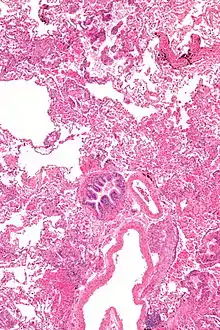

Grossly, LAM lungs are enlarged and diffusely cystic, with dilated air spaces as large as several centimeters in diameter.[105][106] Microscopic examination of the lung reveals foci of smooth muscle-like cell infiltration of the lung parenchyma, airways, lymphatics, and blood vessels associated with areas of thin-walled cystic change. LAM lesions often contain an abundance of lymphatic channels, forming an anastomosing meshwork of slit-like spaces lined by endothelial cells. LAM cells generally expand interstitial spaces without violating tissue planes but have been observed to invade the airways, the pulmonary artery, the diaphragm, aorta, and retroperitoneal fat, to destroy bronchial cartilage and arteriolar walls, and to occlude the lumen of pulmonary arterioles.[105]

There are two major cell morphologies in the LAM lesion: small spindle-shaped cells and cuboidal epithelioid cells.[107] LAM cells stain positively for smooth muscle actin, vimentin, desmin, and, often, estrogen and progesterone receptors. The cuboidal cells within LAM lesions also react with a monoclonal antibody called HMB-45, developed against the premelanosomal protein gp100, an enzyme in the melanogenesis pathway.[107] This immunohistochemical marker is very useful diagnostically, because other smooth muscle–predominant lesions in the lung do not react with the antibody.[108] The spindle-shaped cells of the LAM lesion are more frequently proliferating cell nuclear antigen positive than the cuboidal cells, consistent with a proliferative phenotype.[107] Compared with cigar-shaped normal smooth muscle cells, spindle-shaped LAM cells contain less abundant cytoplasm and are less eosinophilic. Estrogen and progesterone receptors are also present in LAM lesions,[109][110][111] but not in adjacent normal lung tissue.[112] LAM lesions express lymphatic markers LYVE-1, PROX1, podoplanin and VEGFR-3. The smooth muscle–like cells of AMLs are morphologically and immunohistochemically similar to LAM cells, including reactivity with antibodies directed against actin, desmin, vimentin, and HMB-45 as well as estrogen and progesterone receptors.[113][114] Unlike the dilated airspaces in emphysema, the cystic spaces found in LAM may be partially lined with hyperplastic type II cells.[115]